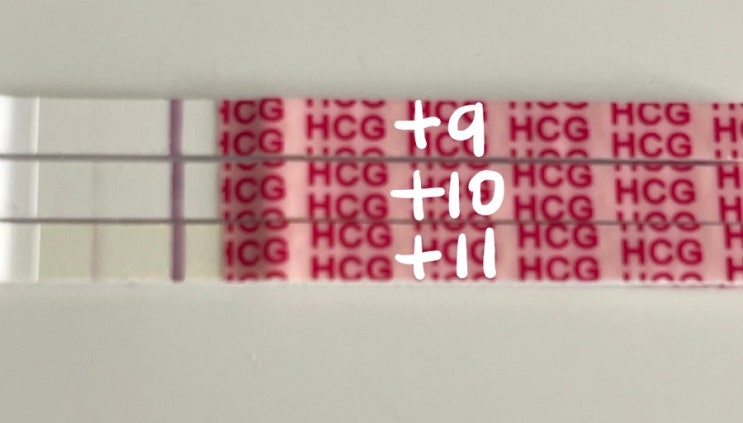

임신일기) 6주차 _ 강동구보건소 임산부선물, 비오템튼살크림, 튼살오일, 풀리오 무선다리마사지기

아기 심장소리도 듣고 했으니 카테고리를 임신일기로 변경해 보았다☺️ 내가 다녔던 난임병원 원장님께서...